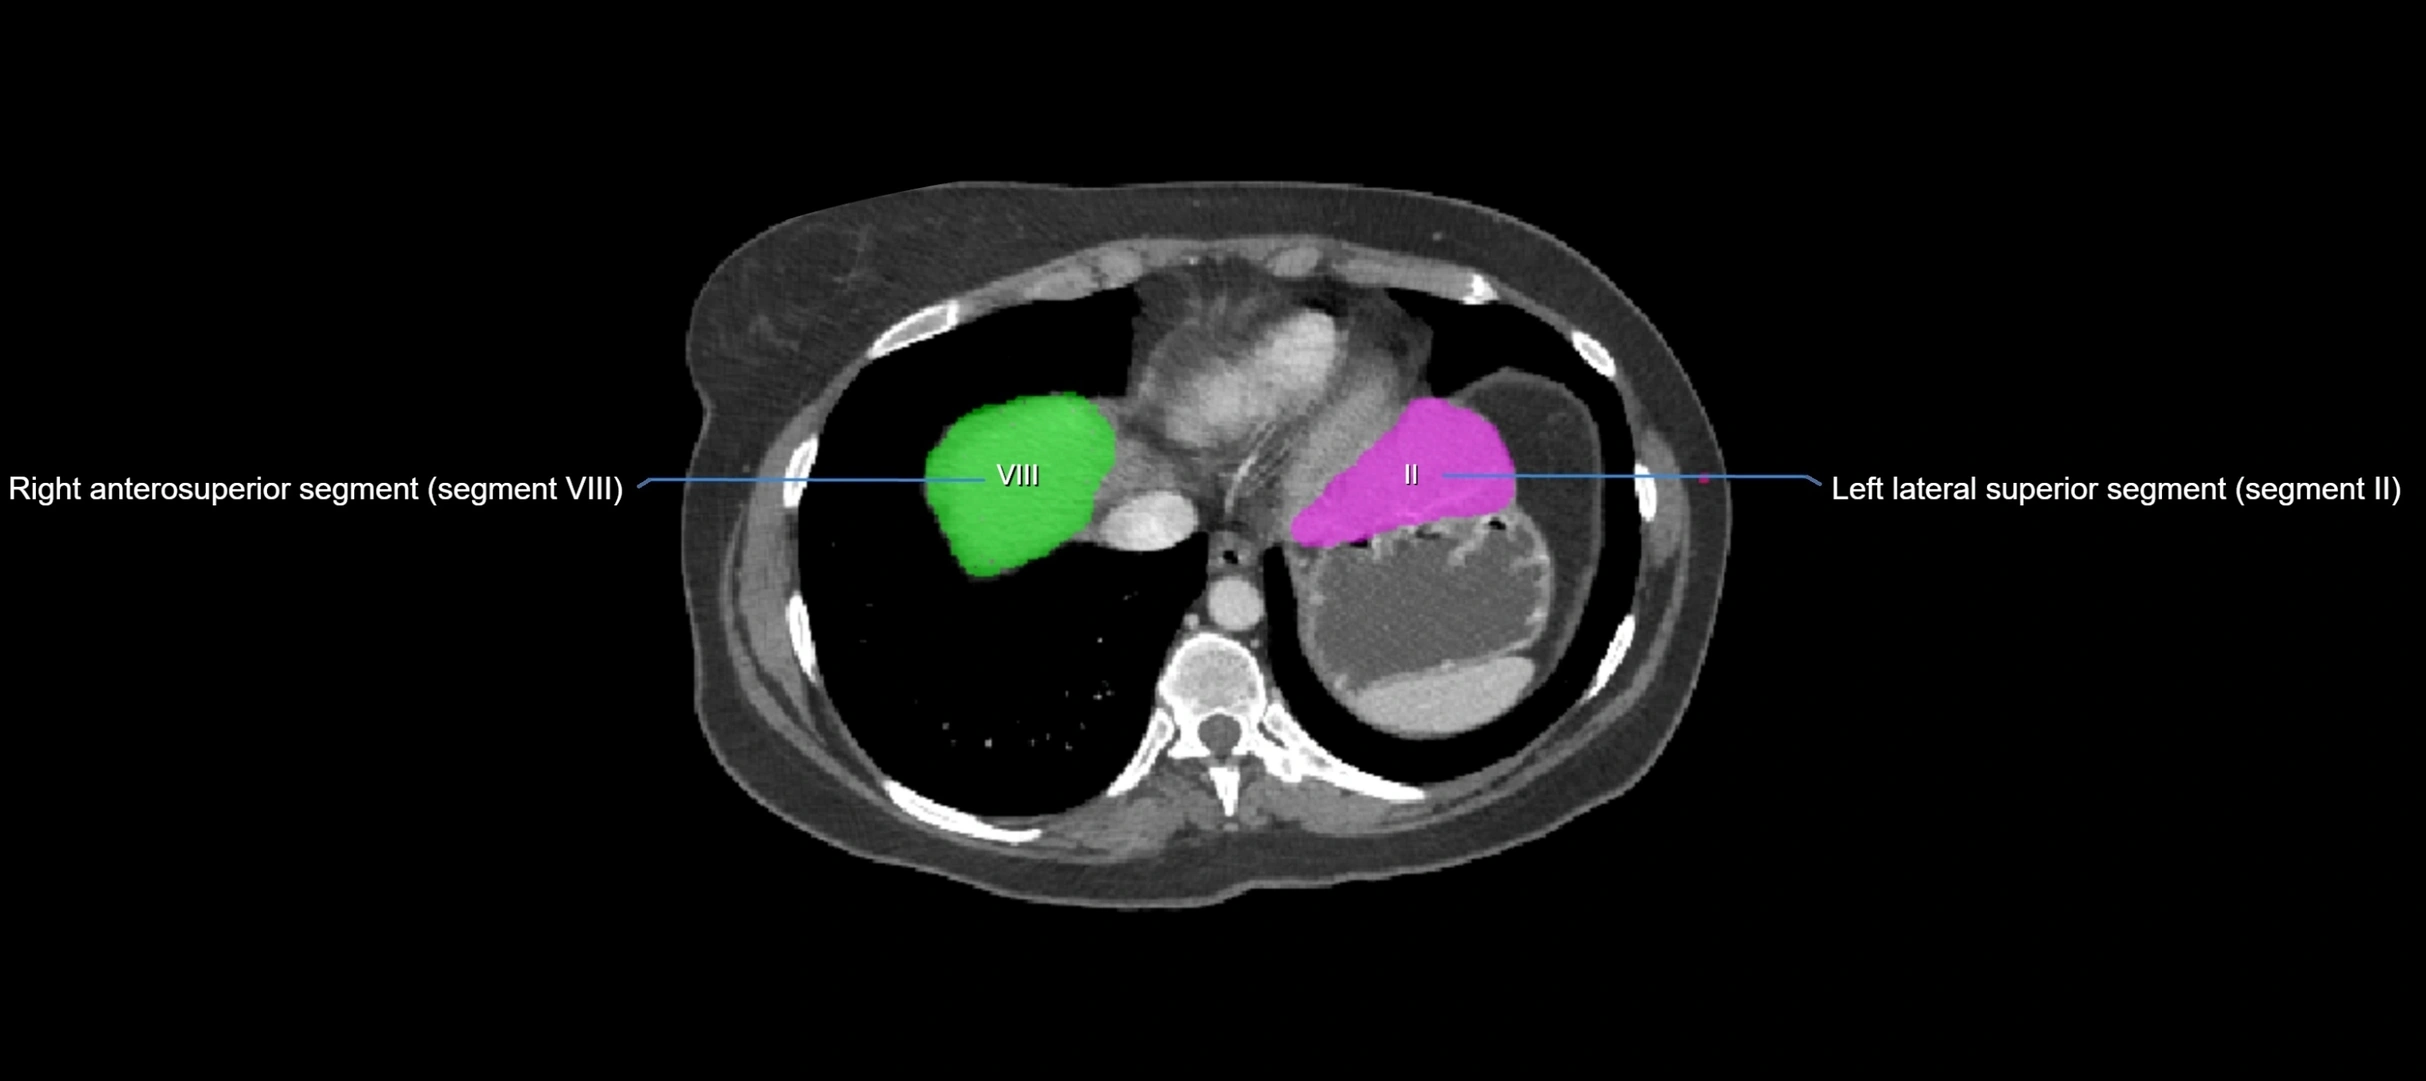

CT Image

image